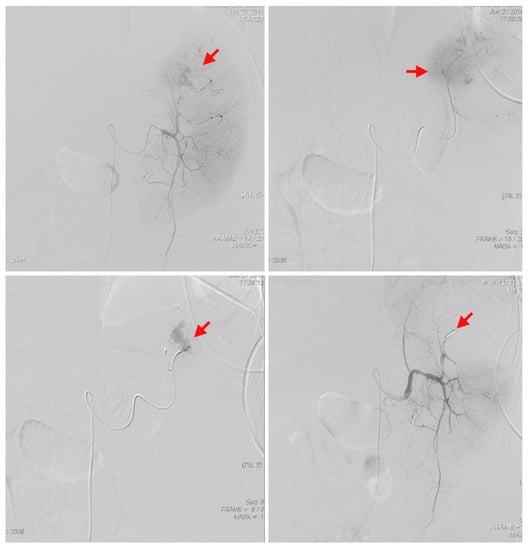

The bedside ultrasound revealed much ascites, which confirmed the emergency abdominal contrast enhanced computed tomography (CT) in the previous transfer hospital and showed splenomegaly and splenic rupture with hemoperitoneum (Figure 1). Adequate fluid resuscitation and emergency blood transfusion were performed to correct the hypovolemic shock status. Transamine (1000 mg) and vitamin K1 (10 mg) were administered to control the bleeding. The opioid agent morphine (10 mg) was used to control progressive abdominal pain. An emergency transcatheter arterial embolization was performed to control persistent splenic hemorrhage (Figure 2).

Figure 2.

An emergency transcatheter arterial embolization was performed using two coils to control splenic hemorrhage (red arrows).